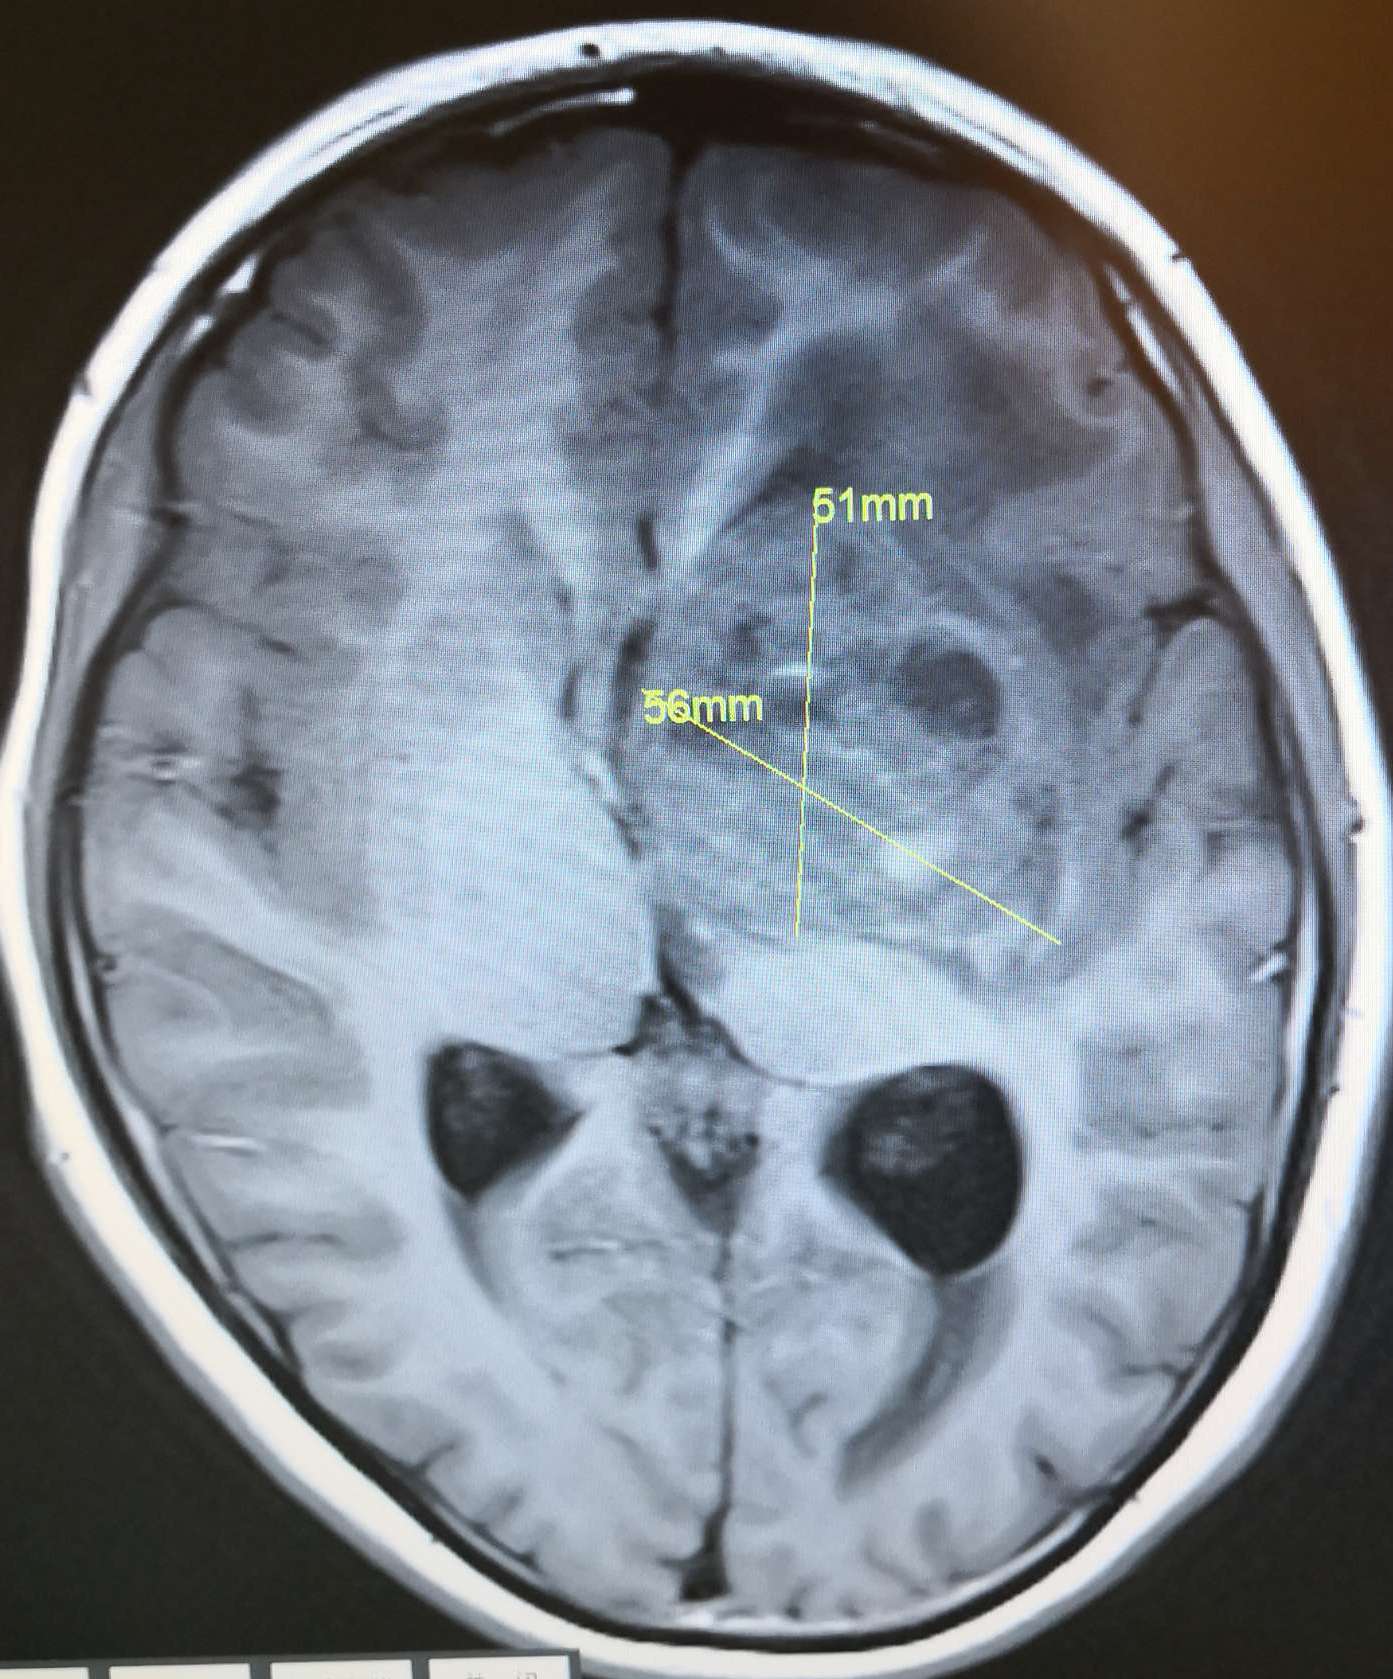

术前头颅MRI T1显示:左侧基底节巨大占位病灶(56*51mm),呈高、低、等混杂信号,脑室受压,中线移位明显。